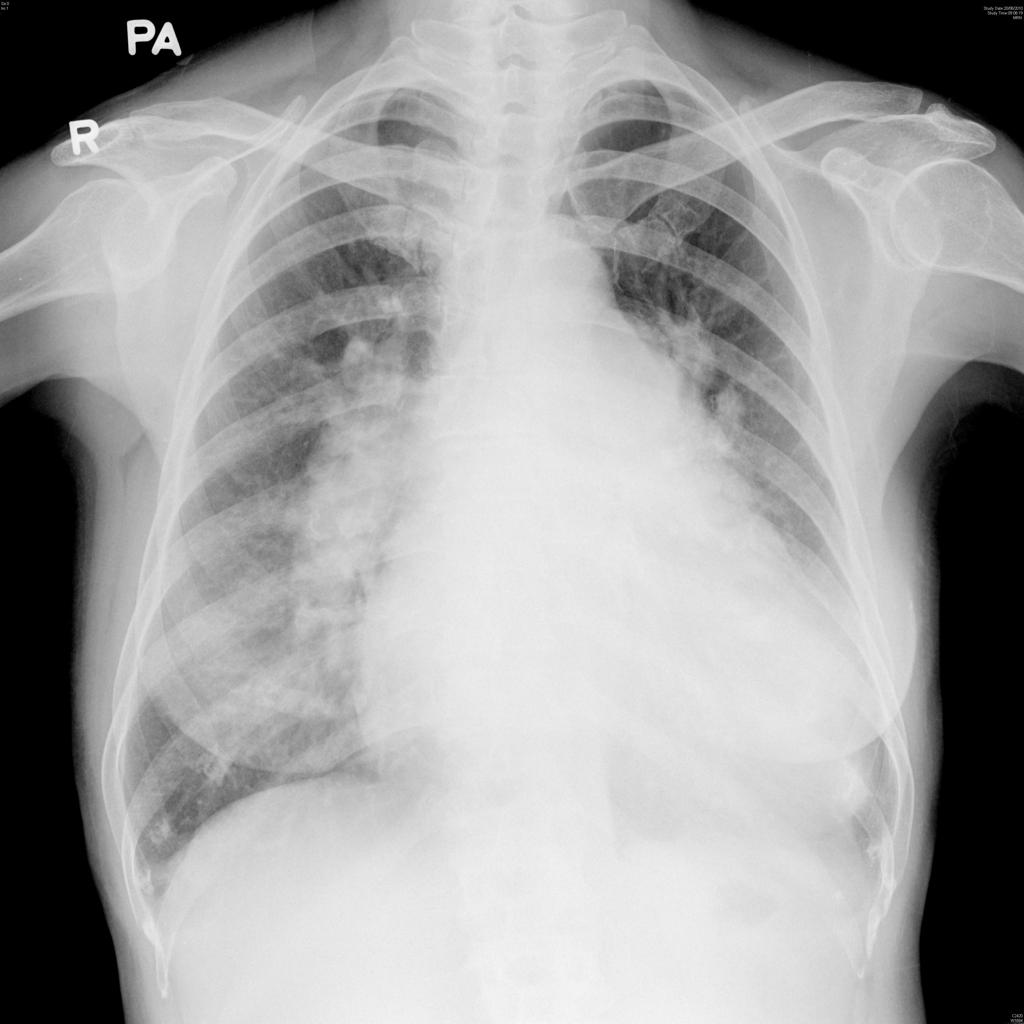

– Tùy thuộc kích thướng lỗ thông hình ảnh X-quang rất khác nhau

+ Lỗ thông nhỏ: hình ảnh X-quang thường bình thường.

+ Lô thông vừa: shunt trái – phải => giãn nhĩ trái và thất trái do tăng gánh tâm trương. Có thể giãn cung động mạch phổi, tăng lưu lượng tuần hoàn phổi chủ động.

+ Lỗ thông lớn: thất phải có thể giãn do tăng gánh tâm thu. Tăng kích thước động mạch phổi, giảm tuần hoàn phổi ngoại biên.

+ Động mạch chủ bình thường hoặc nhỏ do giảm cung lượng tim.

+ Bóng tim to nhưng khi đảo shunt có khuynh hướng thu nhỏ lại gần bình thường, thất phải dày làm mỏm tim hơi tròn và vênh lên cao trên vòm hoành.

+ Giãn cung động mạch phổi và có thể thấy giãn 2 gốc động mạch phổi.

+ Rốn phổi tăng đậm trong khi đó phế trường ngoại vi sáng hơn bình thường tạo hình ảnh cắt cụt điển hình trong phức hợp Eisenmenger.2. Thông liên nhĩ

– Khoảng 15% các trường hợp bóng tim bình thường.

– Luồng thông trái => phải: bóng tim to do giãn nhĩ phải và thất phải, mỏm tim chếch lên. Nhĩ trái và thất trái bình thường.

– Động mạch chủ bình thường hoặc nhỏ hơn do giảm cung lượng tim.

– Cung động mạch phổi giãn do tăng cung lượng => tăng lưu lượng tuần hoàn phổi chủ động.

– Khi tăng áp lực động mạch phổi nặng => đảo chiều luồng thông => động mạch phổi giãn ở trung tâm và co nhỏ ở ngoại vi => phế trường ngoại vi sáng hơn bình thường.

– Nếu ống động mạch nhỏ (< 3mm): hình ảnh X-quang bình thường

– Nếu ống động mạch lớn (> 4mm):

+ Trường hợp còn shunt trái – phải nhiều: dấu hiệu tăng gánh thất trái, buồng tim lớn (nhĩ trái, thất trái), cung động mạch phổi vồng và tăng tuần hoàn phổi chủ động.

+ Khi áp lực động mạch phổi tăng nhiều bóng tim bình thường, tuần hoàn phổi tăng đậm ở gốc, giảm nặng ở ngoại vi.

+ Quai động mạch chủ thường lớn do tăng cung lượng tim.4. Tứ chứng Fallot

– Bóng tim thường không lớn, đôi lúc nhỏ hơn bình thường

– Khuyết cung động mạch phổi (do hẹp động mach)

– Tim hình chiếc giầy (Boot-shaped): thất phải phì đại, mỏm tim chếch lên.

– Tuần hoàn phổi giảm: các động mạch phổi nhỏ => phế trường sáng.

– Quai động mạch chủ thường nằm bên phải (25%)5. Hẹp eo ĐM chủ

+ Phì đại thất trái

+ Mất ấn động mạch chủ

+ Hình số 3 của động mạch chủ: khuyết lõm số 3 là chỗ hẹp, hai chỗ cong là do cung động mạch chủ và phần ngang động mạch chủ đoạn xuống

+ Khuyết sườn (Dấu hiệu Roesler): khuyết bờ dưới cung sườn do giãn động mạch gian sườn. Thường ảnh hưởng các xương sườn 3 đến 8

+ Tuần hoàn phổi thường bình thường